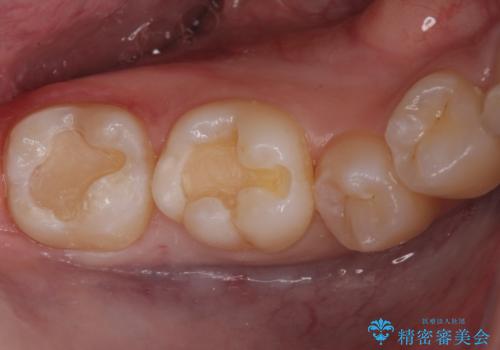

古い樹脂の詰め物を取り除いたところ、歯の神経と非常に近い状態でした。

万一神経と交通した場合に備え、唾液が入らないようにゴムのシートで防湿(ラバーダム防湿)を行い虫歯除去を行いました。

幸い神経とは交通せず、処置後の神経症状もありませんでした。